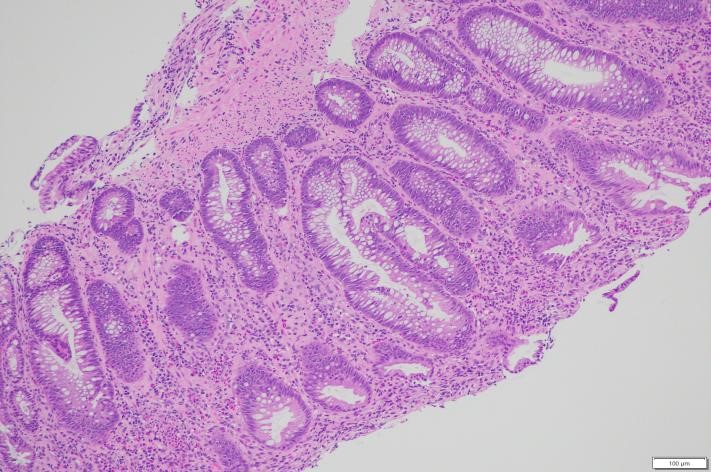

Kết quả mô bệnh học

Trên 04 tiêu bản làm từ bệnh phẩm nhận được, nhuộm HE và PAS thấy:

Ống 1 (đại tràng): Có 03 mảnh sinh thiết niêm mạc đại tràng nhỏ, bề mặt phẳng, tuyến chế nhầy bình thường về số lượng và hình thái. Mô đệm giữa các tuyến phù nề nhẹ, thâm nhiễm rải rác tế bào viêm mạn tính số lượng ít. Không phát hiện dị sản, loạn sản, ung thư, polyp, hình ảnh lao, nấm hay bệnh Crohn.

Ống 2 (đại trực tràng): Niêm mạc dày nhẹ, tuyến chế nhầy có vùng kéo dài nhẹ nhưng vẫn lành tính. Biểu mô phủ có vùng thoái hóa, bong trợt. Mô đệm xen giữa các tuyến thâm nhiễm nhiều tế bào viêm mạn tính và bạch cầu đa nhân trung tính, rải rác có nang lympho. Không thấy dị sản, loạn sản, ung thư, polyp hay viêm đặc hiệu.

Hình 3: Hình ảnh giải phẫu bệnh nhuộm Hematoxylin-eosin x 100